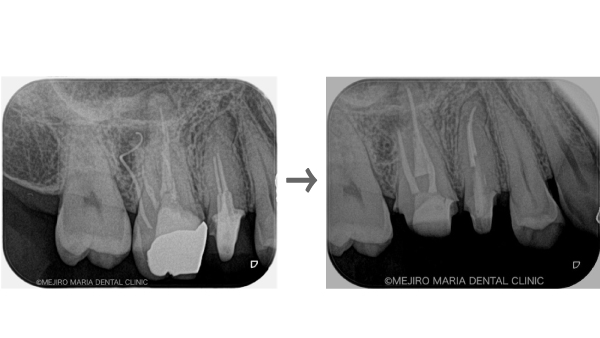

【歯根端切除術】

根管治療を行っても良くならない場合の外科的歯内療法

精密根管治療を施しても治癒に至らない場合、もしくは、被せ物を外すことが困難な場合(装着して間もない被せ物など)は歯根端切除術にて根尖性歯周炎を治癒に導くことが可能です。現代の歯根端切除術の成功率は90%以上で、破折していない歯であれば保存することが可能です。しかし、外科処置なのでリスクも当然あります。当院では精密根管治療初回カウンセリングにてご自身の歯の状態や診断から精密根管治療(歯内療法)後のリスクをお話した上で、治療介入を行うか患者様に決めていただいております。